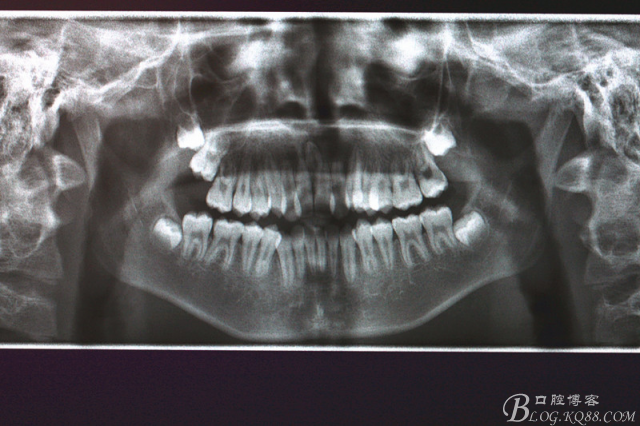

1.術(shù)前全景片